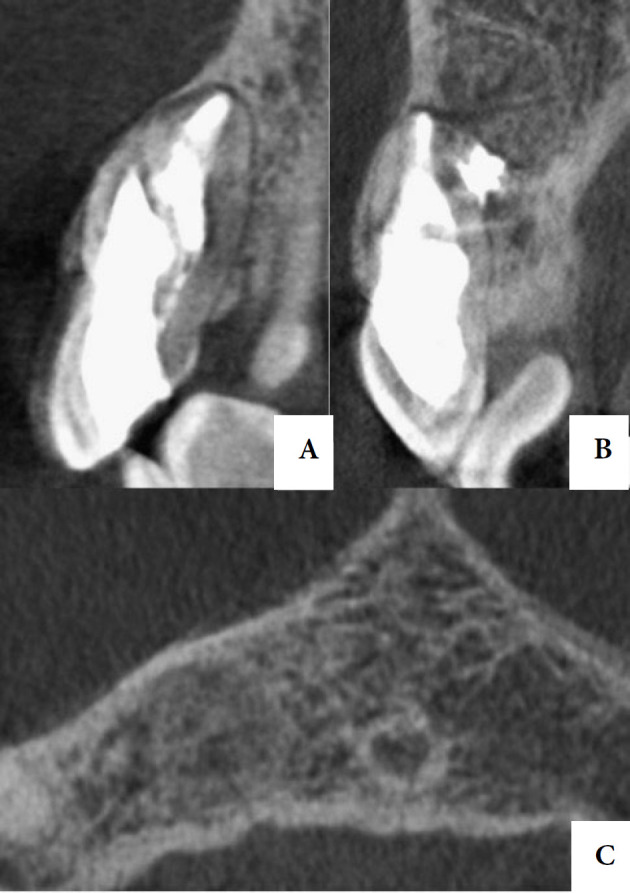

Dens invaginatus (DI) is one of the developmental dental anomalies that results in an invagination of the enamel organ into the dental papila during odontogenesis. The purpose of this study is to report a case of nonsurgical endodontic treatment of an Oehlers type II DI in a right maxillary lateral incisor with an extensive periapical damage, along with the two-year clinical and tomographic follow-up. A 30-year-old patient was referred for endodontic treatment of tooth #12. On clinical examination, a change in the shape and color of the crown was observed. The tooth responded negative to pulp sensibility, percussion, palpation and mobility tests. After tomographic evaluation, an Oehlers type II DI was visualized, in addition to an extensive periradicular lesion. The diagnosis was asymptomatic apical periodontitis. The treatment was carried out in two sessions, through intense enhancement of the auxiliary chemical substance with passive ultrasonic irrigation, XP-Endo Finisher and the use of hydroxide-based intracanal medication. Appropriate treatment in cases with anatomic variations requires an accurate and early diagnosis based on clinical examination and radiographic images. A two-year follow-up of the present case showed that the correct diagnosis associated with appropriate instrumentation techniques, supplementary disinfection, and adequate three-dimensional sealing of the canal with filling material, resulted in regression of the periradicular lesion and bone repair.